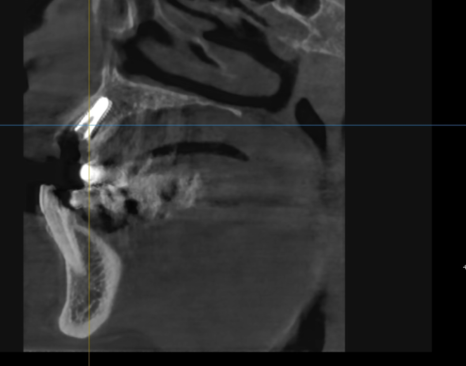

방사선 사진과 CT를 확인해보니

오래된 보철물 안쪽으로

2차 충치가 심하게 진행되어 있었고,

240315

특히 왼쪽 송곳니(#23)는 이미 치아 머리 부분이

부러져 뿌리와 분리된 상태였습니다.

뿌리 끝까지 염증이 퍼져

잇몸뼈가 많이 녹아있었기에,

안타깝게도 발치를 진행하기로 했습니다.

먼저 기존에 사용하시던

오래된 브릿지를 제거한 뒤,

염증이 심해 더 이상 살리기 어려운

치아 4개(#13, 21, 22, 23)를 발치했습니다.